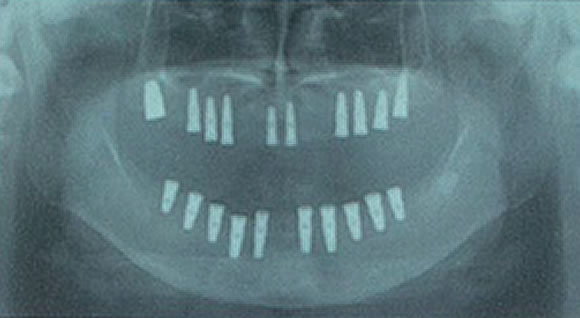

従来の治療法

▲従来の治療法(上下の顎にインプラントを10本づつ埋めこんだレントゲン)

従来、すべての歯を失った方にインプラント治療を行う場合、骨の移植をしたり、8~14本のインプラントを埋め込むのが一般的でした。

そのため手術時間が長くなり、術後の腫れも大きく、費用がかさむという不安要素がありました。